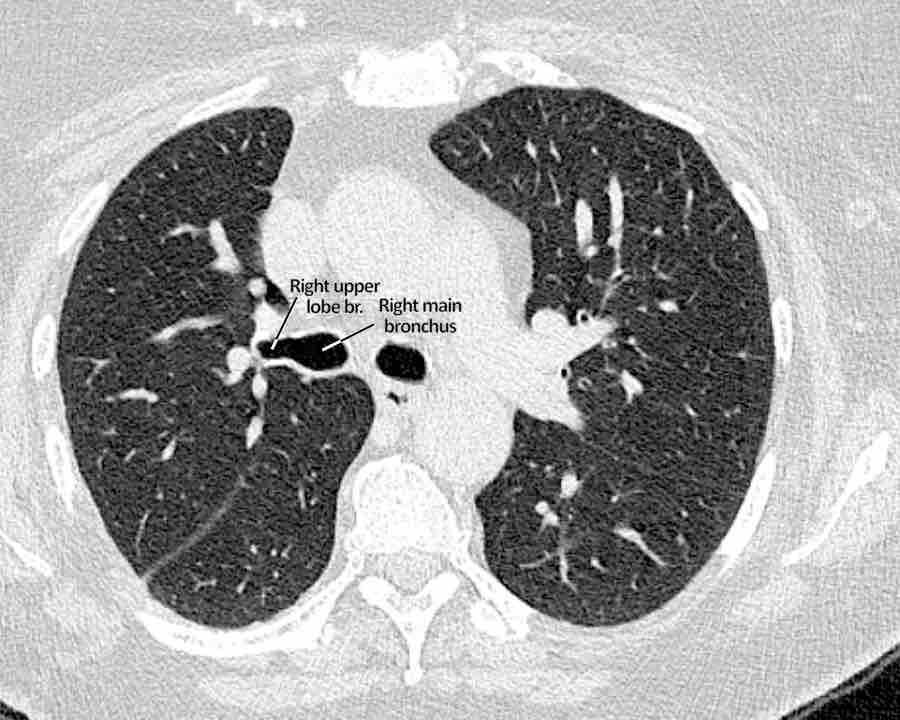

Phế quản trên CT

Cuộn qua các hình ảnh để quan sát khí quản phân chia thành phế quản chính phải và trái, sau đó tiếp tục phân chia thành các phế quản thùy và phế quản phân thùy.

Phế quản thùy trên, phế quản trung gian và phế quản thùy dưới tiếp tục đi về phía ngoại vi.